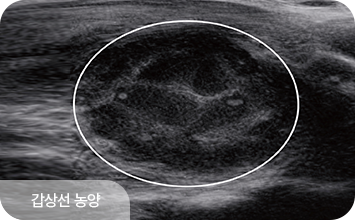

결절이 발견된 경우에는 초음파 소견을 바탕으로 판독 후,

필요에 따라 세침흡인검사 또는 총조직검사를 시행합니다.

갑상선 결절의 악성 여부를 판단하는 데 가장 흔히 시행되는 방법으로,

갑상선 세침검사는 아주 가는 바늘을 사용해 갑상선 결절에서

세포를 소량 흡인한 뒤 현미경으로 세포의 모양을 분석하여

양성인지 악성 가능성이 있는지 확인하는 검사입니다.

갑상선 질환은 결절의 크기보다,

구조적 특성과 변화 양상을 함께 살펴야 합니다.